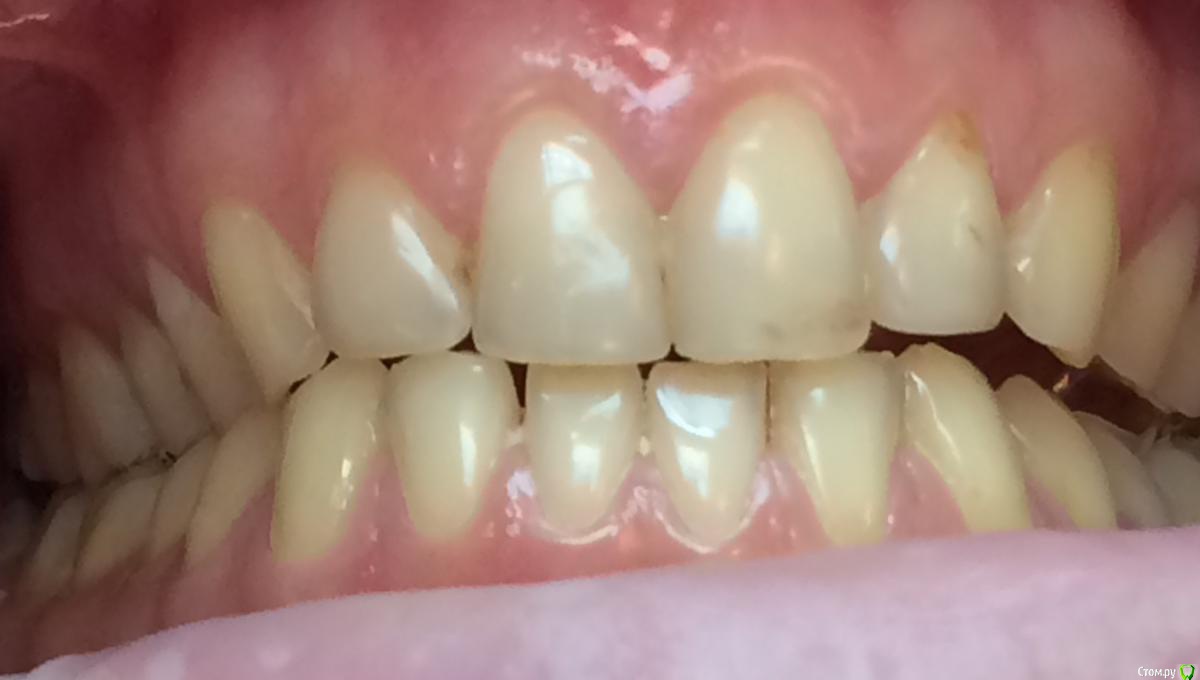

Larnary Опубликовано 28 июля, 2015 Поделиться Опубликовано 28 июля, 2015 (изменено) Добрый день!Ко мне обратилась пациент 1988 гр с жалобой на стираемость зубов и постоянные сколы пломб.Объективно небная поверхность верхних резцов стерта до дентина. Окклюзионная стираемость жевательной группы зубов.Прошу помочь с выявлением причины такой стираемости зубов и оптимальноно метода лечения Изменено 28 июля, 2015 пользователем Larnary Ссылка на комментарий

Bobby Опубликовано 29 июля, 2015 Поделиться Опубликовано 29 июля, 2015 Фасетки стираемости на нёбных поверхностях верхних резцов и вестибулярных поверхностях нижних резцов обусловлены малым оверджетом - недостаточная щель по саггитали, поэтому и будут колоться реставрации, а ткани зубов истираться. Фрадеани про это на своём курсе рассказывал и показывал видео как это диагносцировать и что с этим делать. Что вообще хочет пациентка и на что готова? Эти вопросы лучше сразу решать на первичной консультации, а то делаете диагностики, всё рассчитываете, распинаетесь, а они потом: "ой, я пока не готов/а к такому плану лечения" и всё заканчивается композитной мазнёй в другой клинике. 5 Ссылка на комментарий

zzkz Опубликовано 29 июля, 2015 Поделиться Опубликовано 29 июля, 2015 Со слов Коиса понял, что в данном случае было бы достаточно создать достаточное функциональное пространство для резцов нижней челюсти, путем брекетов например, вывести передние резцы в/ч в протрузию Ссылка на комментарий

Bobby Опубликовано 29 июля, 2015 Поделиться Опубликовано 29 июля, 2015 Со слов Коиса понял, что в данном случае было бы достаточно создать достаточное функциональное пространство для резцов нижней челюсти, путем брекетов например, вывести передние резцы в/ч в протрузиюИменно! А иногда это пространство можно создать за счёт легкого изменения угла коронковой части зубов (за счёт керамических рестарваций - если к ним есть показания, а в данном случае они как раз есть). Ссылка на комментарий

Maverick Опубликовано 9 августа, 2015 Поделиться Опубликовано 9 августа, 2015 (изменено) Думаю в данном кейсе интрузия резцов будет нежелательна, десневые контуры фронтальной группы зубов выглядят хорошо, ровно, нет разницы в высоте(если конечно не были внесены изменения в контур десны, типа пластик) . И тут не дентальный глубокий прикус, а скелетный, как было отмечено выше. Еще один негативный момент в интрузии, который играет важную роль , так это искусственное состаривание пациента, верхняя губа имеет свойство опускаться со временем, что только ухудшит картину эстетики улыбки. Экспозиция резцов очень важный критерий в планировании лечения, тут надо отталкиваться от возраста пациента. Думаю у данного пациента, учитывая возраст, позицию фронтальных зубов , уровень десны идеально будет завысить прикус в боковом отделе и вывести в небольшой вестибулярный наклон фронт на брекетах, либо как упоминалось выше за счет изменение наклона коронковой части, путем керамических реставраций, что удобнее для пациента в плане финансовых и временных затрат. P.S. Такое ощущение , что есть определенные проблемы с клыковым ведением, поэтому и интерфреннции возникают в боковом отделе. Поэтому хорошо было бы увидеть все в артикуляторе, чтобы уже точно знать причину Угол межрезцовый идеальный 132 градуса плюс минус 10 град. Изменено 9 августа, 2015 пользователем Maverick 2 Ссылка на комментарий